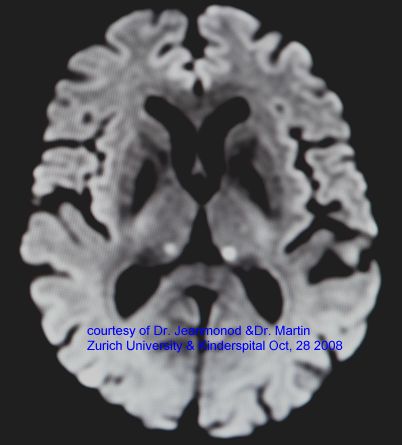

Together, we revisit key milestones – from the first MRgFUS based thalamotomy in 2008 and early applications in breast cancer, to the expanding frontiers of neuromodulation. Looking ahead, we discuss the exciting possibilities of blood brain barrier opening, the acoustic neurosurgical suite, and even brain mapping through focused sound.